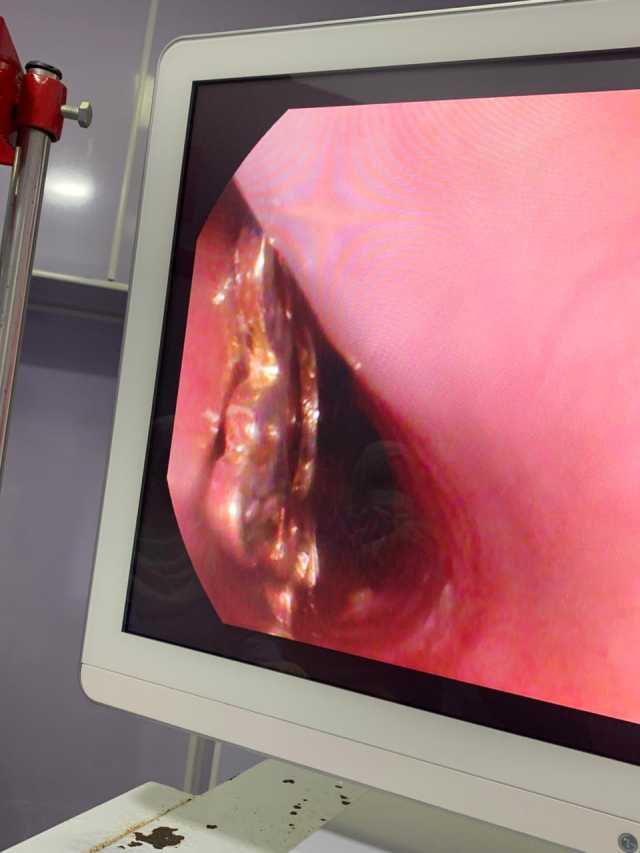

وأوضح الدكتور أحمد البيلي وكيل وزارة الصحة أن قسم المناظير بمستشفى أبو كبير شهد نجاح مميز في إنقاذ الطفلة التي تبلغ من العمر ٥ سنوات، وقامت بابتلاع سلسلة معدنية حادة ومدببة وأطرافها قادرة على إحداث جروح أو ثقوب بالزور أو داخل المعدة، وبعد استقبالها مساء أمس الثلاثاء بمستشفى مشتول السوق المركزي، وتم التنسيق السريع من خلال مركز الخدمات الطارئة ١٣٧ بالمديرية، وتحويل الحالة بسيارة الإسعاف إلى مستشفى أبو كبير في وقت قياسي، وتم التدخل العاجل بالمنظار بعد إجراء كافة الفحوصات الطبية اللازمة لها، واستخراج السلسلة من المعدة دون أي مضاعفات، وسط متابعة وتدخل فوري من الفريق الطبي بقيادة الدكتور محمد عصام خلال الفترة المسائية.